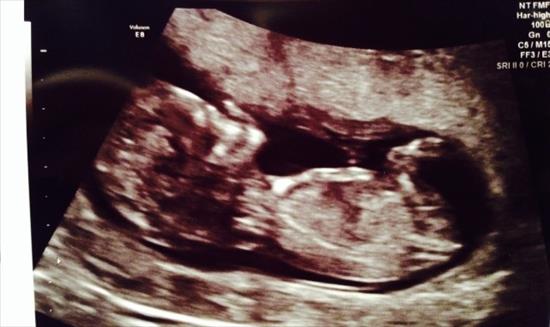

Can anyone see the nub in this ultrasound photo taken 12w 1d ? Predictions welcome !!

no visible nub. At 12w 1d it would still be a 50/50 guess

I don't see a nub. :(